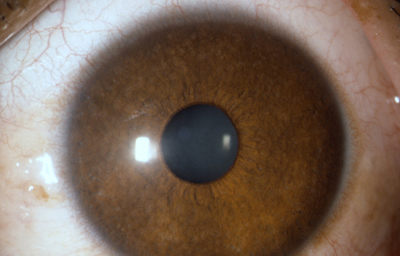

En los humanos y en la mayoría de los mamíferos y pájaros, el Iris es una estructura anular en el ojo, responsable de controlar el diámetro y tamaño de la Pupila y controlar así la cantidad de luz que penetra al Ojo. En términos de la Optica, el Iris es el diafragma y la pupila su apertura. El color del ojo se define según el color del Iris.

El Iris consta de fibras musculares lisas, circulares y radiales dispuestas en una estructura en forma de rosca en el estroma. El músculo Sphinter Pupillae es circumferencial y contrae la pupila con un movimiento circular, esta inervado por el 3er para craneal ( nervio Motor Ocular Común) en el que las fibras parasimpáticas partiendo del núcleo de Edinger -Westphal situado en el tronco cerebral, llegan a la pupila través de los nervios ciliares cortos; es antagonista al músculo circular-radial dilatador, Dilator pupillae, el cual hala el iris radialmente para abrir la pupila formando pliegues circulares en el estroma ciliar; es inervado por neuronas postganglionares simpáticas localizadas en el ganglio cervical superior; sus axones pasan a la rama oftálmica del Trigémino y por los nervios ciliares largos llegan al Iris. - La contracción o la dilatación en el Iris, es un reflejo fisiológico para adaptar la visión a la luminosidad del ambiente.